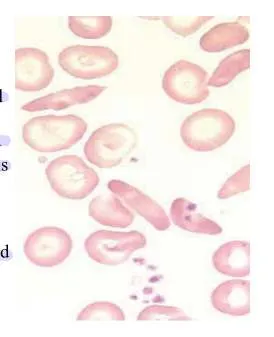

- A 20-year-old male presented with Hb 10 mg/dl, MCV 66 fl, recently on isoniazid for TB. Attached blood smear.

Characterized by the presence of increased serum iron, ferritin, and transferrin saturation as well as ringed sideroblasts

microcytic, hypochromic cells alongside normocytic cells), possibly Pappenheimer bodies (iron granules in RBCs

- The acquired form: drugs such as chloramphenicol, isoniazid, or alcohol

- High serum iron (the only microcytic anemia with elevated iron)

- Prussian blue stain (most specific test) of RBCs in the marrow will reveal the ringed sideroblasts.

- Treatment: Remove the offending drug. Consider transfusion for serious cases.